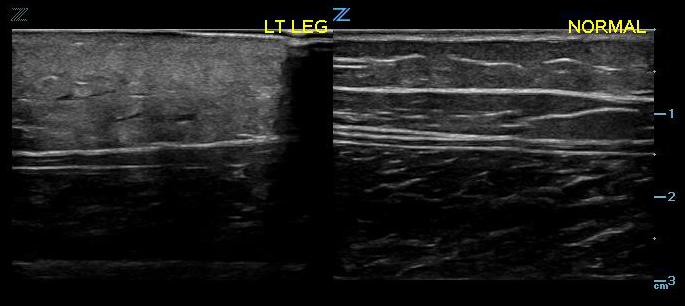

- The subcutaneous layer appears hypoechoic on ultrasound, with two components: hypoechoic fat interspersed with hyperechoic linear echoes running mostly parallel to the skin, which represent connective tissue septa (Fig. 2).3

- Figure 2. Normal skin, subcutaneous tissue, and fascia

- Fascia appears as a linear hyperechoic layer. Its thickness will vary depending on the location.4

- Figure 3. Early cellulitis (left) compared with normal (right)